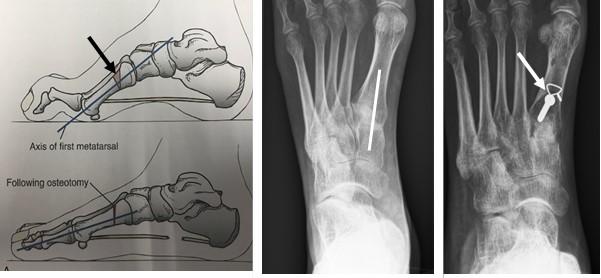

Jones Procedure

Bij de Jones procedure wordt de lange strekpees van de grote teen verplaatst van het eindkootje naar het middenvoetsbeentje van de grote teen. De beide kootjes van de grote teen worden aan elkaar vastgezet met een schroef. Deze procedure zorgt ervoor dat de strekpees van de grote teen de teen niet meer doet klauwen maar zorgt juist voor een omhoogwaartse beweging van de grote teen. Dit gaat weer de holvoet tegen.

Figuur 5: Op het linker plaatje is de grote teen zichtbaar. Er worden 2 littekens gemaakt. De pees wordt losgehaald bij het eindkootje en door het middenvoetsbeentje gevlochten door een boorgat. Op de rechter foto is de schroef zichtbaar die beide kootjes aan elkaar verbindt. Deze wordt vanuit het puntje van de teen geboord middels een (klein) 3e litteken. De witte streepjes geven de locatie van de andere 2 littekens aan.